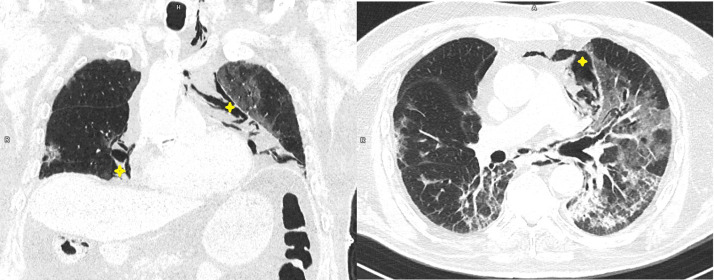

A control computerised tomography scan (CT) performed on day 19 (Fig. 1 ) showed a tendency towards fibrosis and pneumomediastinum dissecting to the cervical region. The fraction of inspired oxygen was increased with almost complete improvement shown by imaging six days later, and he was discharged after 27 days.

Fig. 1.